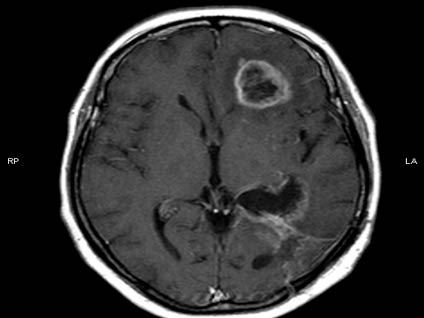

Anasayfa Video Beyin tümörü nasıl oluşur?